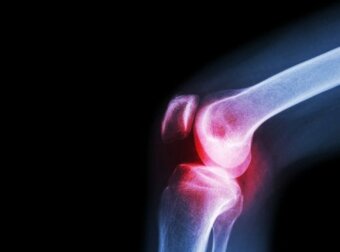

È importante sottolineare che la maggior parte dei casi sono causati da batteri, in particolar modo da stafilococchi e streptococchi. La malattia può presentarsi a qualsiasi età, ma è più frequente nei neonati. Le articolazioni più colpite sono sono l’anca e il ginocchio.

In alcuni casi si rende necessaria una radiografia dell’articolazione interessata. Le radiografie e altri esami di diagnostica per immagini aiutano a formulare la corretta diagnosi.